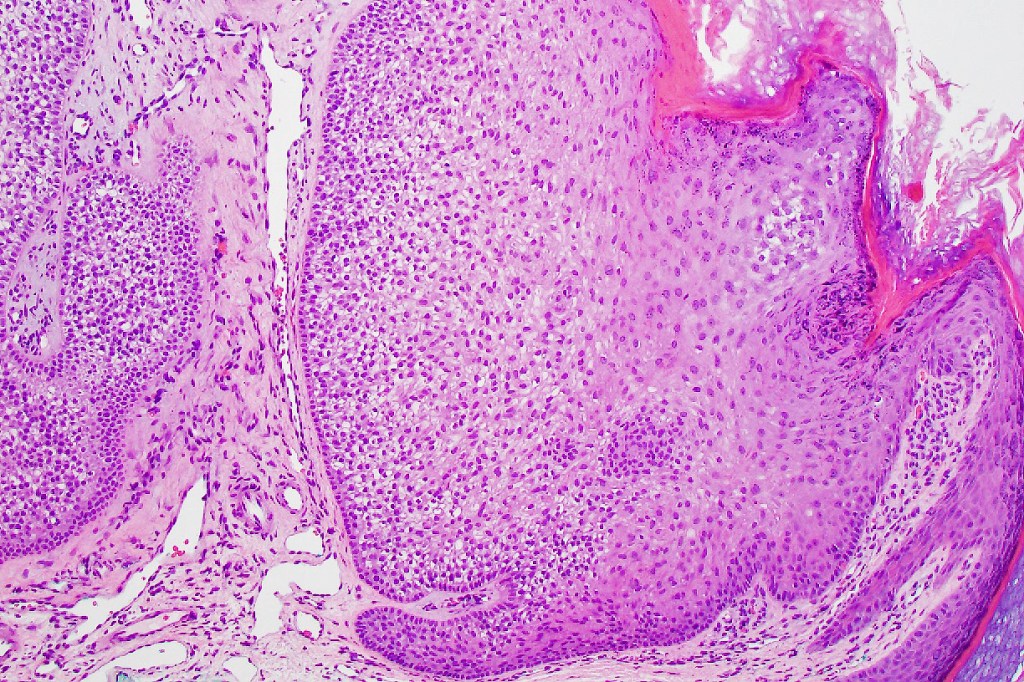

Histologicla features

•Multilobular growth connecting with epidermis & sometimes adjacent follicular external root sheath

•Small epithelial cells with often vacuolated cytoplasm and showing peripheral palisading

•Eosinophilic thick basement membrane

Histological features

•Typical trichilemmoma surrounding a densely, hyalinized collagenous region containing narrow epithelial strands sometimes mimicking a carcinoma